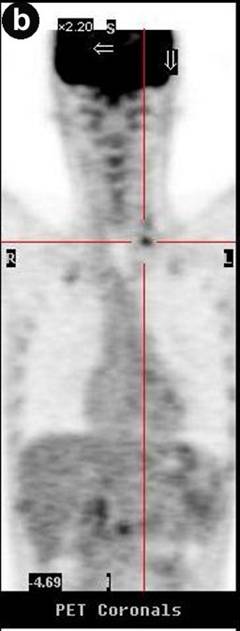

A 51-year-old Caucasian male presented with a history of progressive jaundice, loss of weight, acholic stools, and bilirubinuria. He was found to have a pancreatic head mass on a transabdominal ultrasound and CT scan of the abdomen. Fine needle aspiration cytology (FNAC) of the pancreatic mass confirmed well-differentiated ductal adenocarcinoma. The patient had unresectable disease given that the tumor encased approximately 180 degrees of the superior mesenteric artery. The initial CT scan of the abdomen showed nodules in the liver that were suspicious but not confirmatory for metastasis. Therefore, PET/CT scan was performed where no liver metastases were noted. CT scan of the neck did not demonstrate any evidence of supraclavicular metastasis (Figure 1). However, there was uptake of 18-fluorodeoxyglucose (FDG) with a standard uptake value (SUV) of 4.3-4.7 in the medial left supraclavicular region that was suspicious for nodal metastasis (Figures 2 and 3). FNAC of the left supraclavicular lymph node showed poorly differentiated metastatic adenocarcinoma consistent with a pancreatic primary. Therefore, the final clinical staging was stage IV (T4NXM1, Table 1).

Figure 2. PET scans of Patient #1 before (a.) and after (b.) chemotherapy showing supraclavicular metastasis. |

Figure 3. PET/CT scans of Patient #1 before (a.) and after (b.) chemotherapy showing supraclavicular metastasis. After 5 cycles of chemotherapy, PET/CT scan (b.) shows favorable response to therapy with decrease in SUV of supraclavicular lymph nodes from 4.3-4.7 (baseline, a.) to 2.4 (b.). |

After confirmation of metastatic disease, the patient was started on gemcitabine 1,000 mg/m2 and nab-paclitaxel 100 mg/m2, both intravenously (i.v.) on days 1, 8, and 15 with cycles repeated every 28 days. At the most recent presentation, the patient had completed five cycles of systemic chemotherapy with gemcitabine and nab-paclitaxel. His CA 19-9 level had declined from 962 U/mL at baseline to 444 U/mL (reference range: 0-55 U/mL) and his PET/CT and CT scans demonstrated a favorable response to therapy. Notably, his PET/CT scan showed a decrease in SUV in the left supraclavicular nodal metastasis from 4.3-4.7 at baseline to 2.4 (Figure 3).

In all of the three cases reported in this article, PET/CT scans detected supraclavicular lymph node involvement that was not identified by the standard imaging protocol, CT scan of the chest and abdomen, for pancreatic cancer. Of note, CT scans, which are the de facto surveillance imaging modality, failed to detect metastasis in all three cases (Figure 1). Of course, this was predominantly due to the fact that CT scans of the neck would not be part of a routine surveillance algorithm for patients with pancreatic cancer.